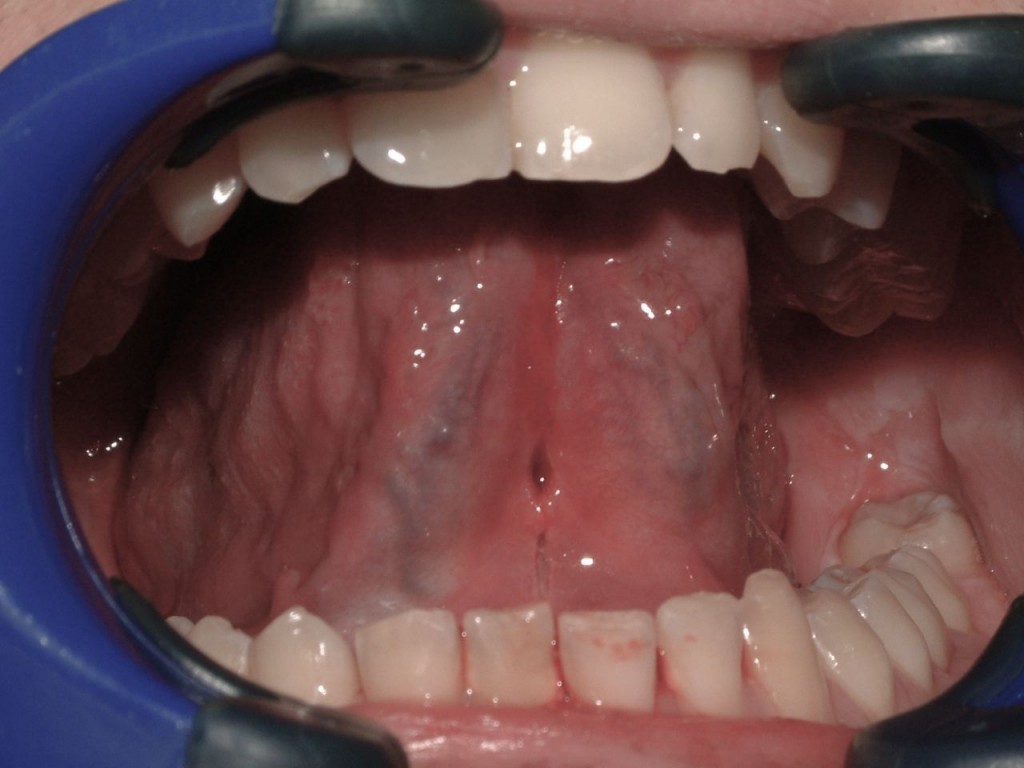

Frenectomy Before and After Cosmic Smile Laser Dental Dental Laser Frenectomy Prevent speech & airway issues with your kids. It also allows for more precision, making it a safer and more effective option for babies and. Laser frenectomy, on the other hand, uses a laser to remove the frenulum. Sometimes a small fold of tissue exists either below the. The laser cauterizes the wound, reducing the risk of infection and bleeding.. Dental Laser Frenectomy.